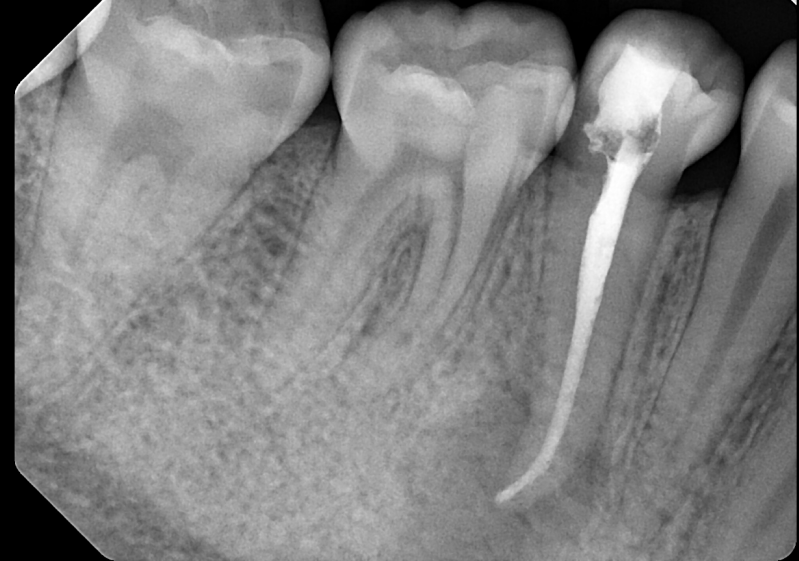

Case: RCT on Tooth #9

67-year-old male, diabetes, no known drug allergies.

Dx: Pulp necrosis and chronic apical abscess.

Tx: Root canal therapy.

Reflection

The main challenge in this case was negotiating calcified canals through an existing crown. Locating the orifice was difficult, but persistence paid off. The final X-ray showed a sealer puff from an accessory canal—right where the sinus tract had traced—suggesting thorough cleaning. With proper disinfection, we’re hopeful this will lead to healing of the fistula. The sealer puff is evident and, given its biocompatibility, not a major concern, though follow-up is essential.